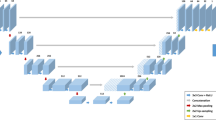

Under IRB approval, patients who underwent routine 3-T lumbar spine (L-spine) MRI from August 17 to September 17, 2020, with both isotropic 3D and 2D T2w-FSE sequences, were retrospectively included. A DLRecon algorithm, with denoising and sharpening properties was applied to SOC 3D k-space to generate 3D DLRecon images. Four musculoskeletal radiologists blinded to reconstruction status evaluated randomized images for motion artifact, image quality, central/foraminal stenosis, disc degeneration, annular fissure, disc herniation, and presence of facet joint cysts. Inter-rater agreement for each graded variable was evaluated using Conger’s kappa (κ).